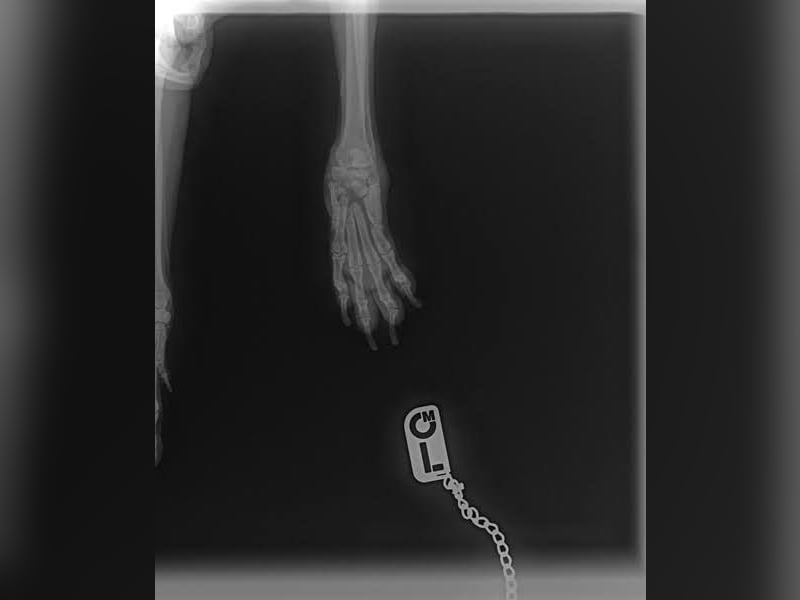

Bemerkungen: Scotti hat Probleme mit seiner Pfote, denn auf ihn wurde geschossen.

Auf Scotti wurde geschossen. Er wurde schwer an der Vorderpfote verletzt und er wurde dann auch einfach liegen gelassen. Glücklicherweise wurde der Tierschutz verständigt und Scotti wurde direkt in ärztliche Obhut gebracht. Dies alles geschah in der zweiten Januarwoche 2025.

Die Genesung von Scotti dauerte sehr lange, aber alle Bemühungen haben sich gelohnt und Scotti hat auch alle Anwendungen brav und geduldig ertragen. Die Verletzung ist aktuell verheilt, aber Scotti wird wohl sein ganzes Leben humpeln.